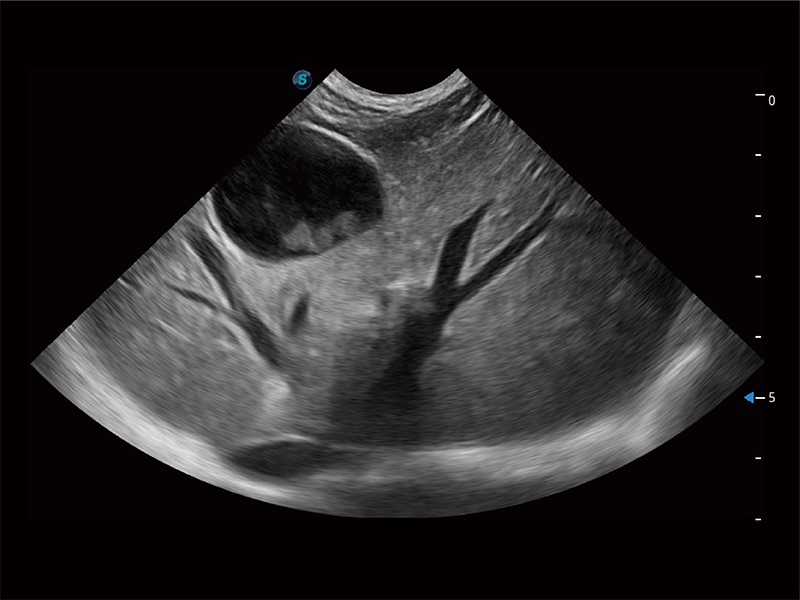

ProPet 80 配备了丰富的心脏探头群、先进的成像技术和专业的心脏测量工具,可帮助动物医生为不同体型和生理结构的动物提供心脏和心肌功能的全面评估。

ProPet 80 专为动物医生设计,对不同的动物体型和生理结构作出了针对性的优化。通过动物影像专用软件,可满足个性化的应用需求,帮助动物医生获得更精确的诊断数据。